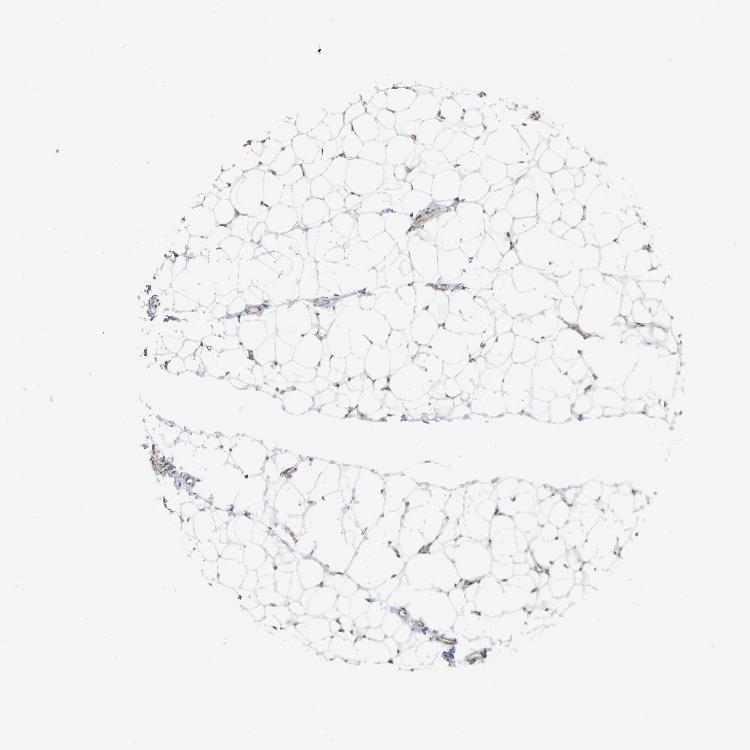

SOFT TISSUE 1 - Antibody stainingi

Antibody staining in the annotated cell types in the current human tissue is reported as not detected, low, medium, or high, based on conventional immunohistochemistry profiling in selected tissues. This score is based on the combination of the staining intensity and fraction of stained cells.

Each image is clickable and will lead to virtual microscopy that enables deeper exploration of all samples and also displays staining intensity scores, fraction scores and subcellular localization as well as patient and tissue information for each sample.

Antibody HPA001923Antibody HPA003908

Chondrocytes Not detected-

Fibroblasts Not detectedNot detected

Peripheral nerve MediumLow